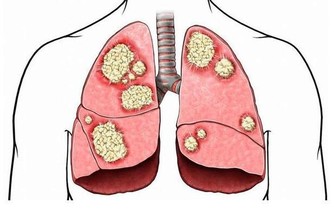

它會引起動脈粥樣硬化,導致心血管疾病;

而當血脂積累過多就會沉積在血管壁上,並逐步形成動脈粥樣硬化斑塊,造成血管變得狹窄,從而導致心腦血管疾病風險蹭蹭漲~